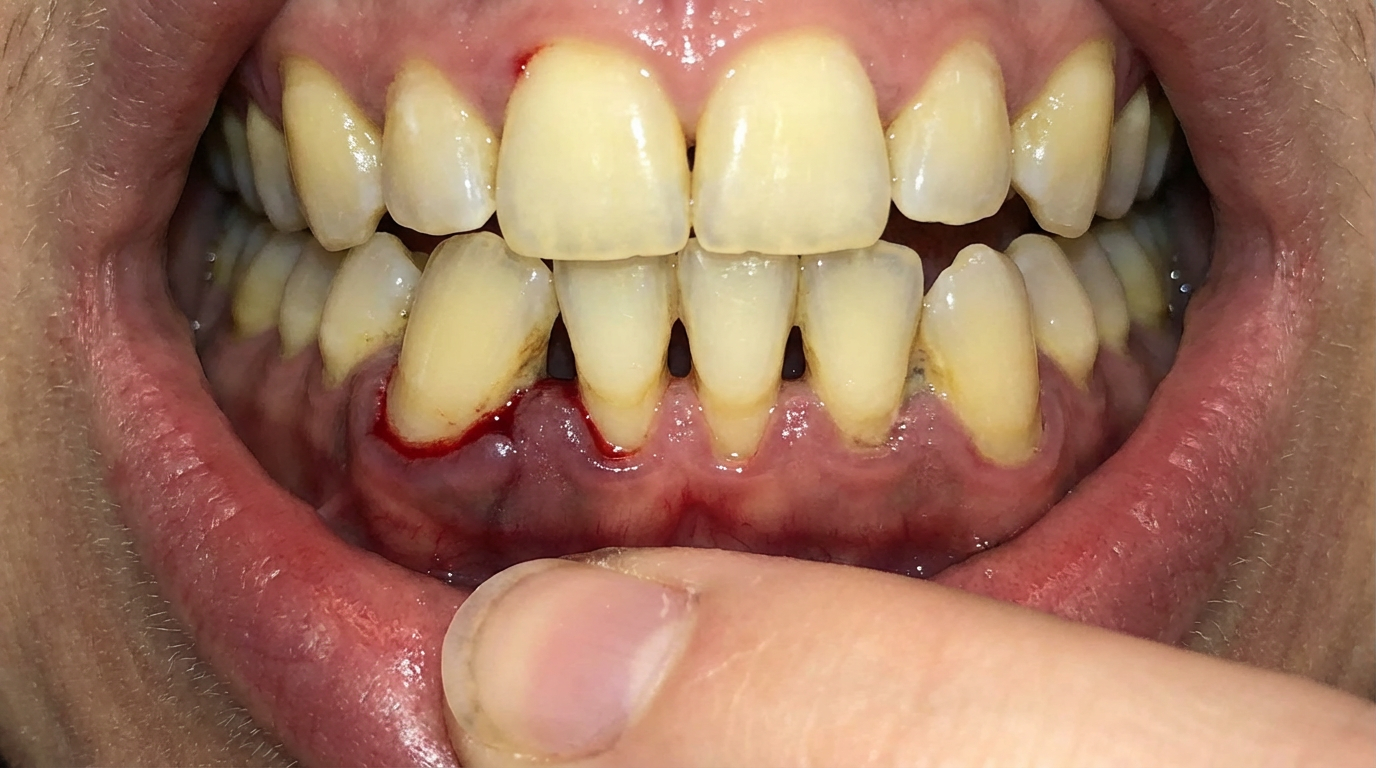

The 10-Second Mirror Test

Try this right now.

Go to your bathroom mirror. Pull your lower lip down gently. Look at where your gums meet your teeth.

Can you see more tooth than you remember?

Is the gum line uneven? Darker in some places? Puffy? Does one tooth look “longer” than it used to?

If so, what you’re looking at is gum tissue that has already pulled away from your teeth. Tissue that is already gone.